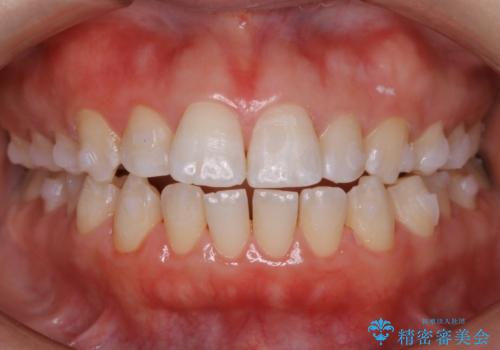

【非抜歯】上下の前歯が噛み合わないオープンバイトの治療

- 噛み合わせの不調を主訴にご来院されました。

骨格的な問題もあり、噛んだ時に奥歯しか当たらず前歯の被蓋があまりない状態でした。

奥歯を沈めて噛み込みを深くしていくことで被害の改善が起こるとともに、下顎自体が前上方に回転移動することで顔貌的にも変化を出すことができます。

臼歯の位置が高く噛んだ時に奥歯しか当たらなかったり、舌癖などが原因で前歯が前に倒れてしまうことで上下の前歯の被蓋がなくなってしまっている状態をオープンバイトといいます。

前者の場合は臼歯を圧下し沈めてあげることで改善させます。後者の場合は前方に傾斜している歯を元の角度に戻してあげることで改善しますが、舌癖がある場合はその癖自体を無くす治療をしない限りまた同じ状態へと後戻りしてしまいます。